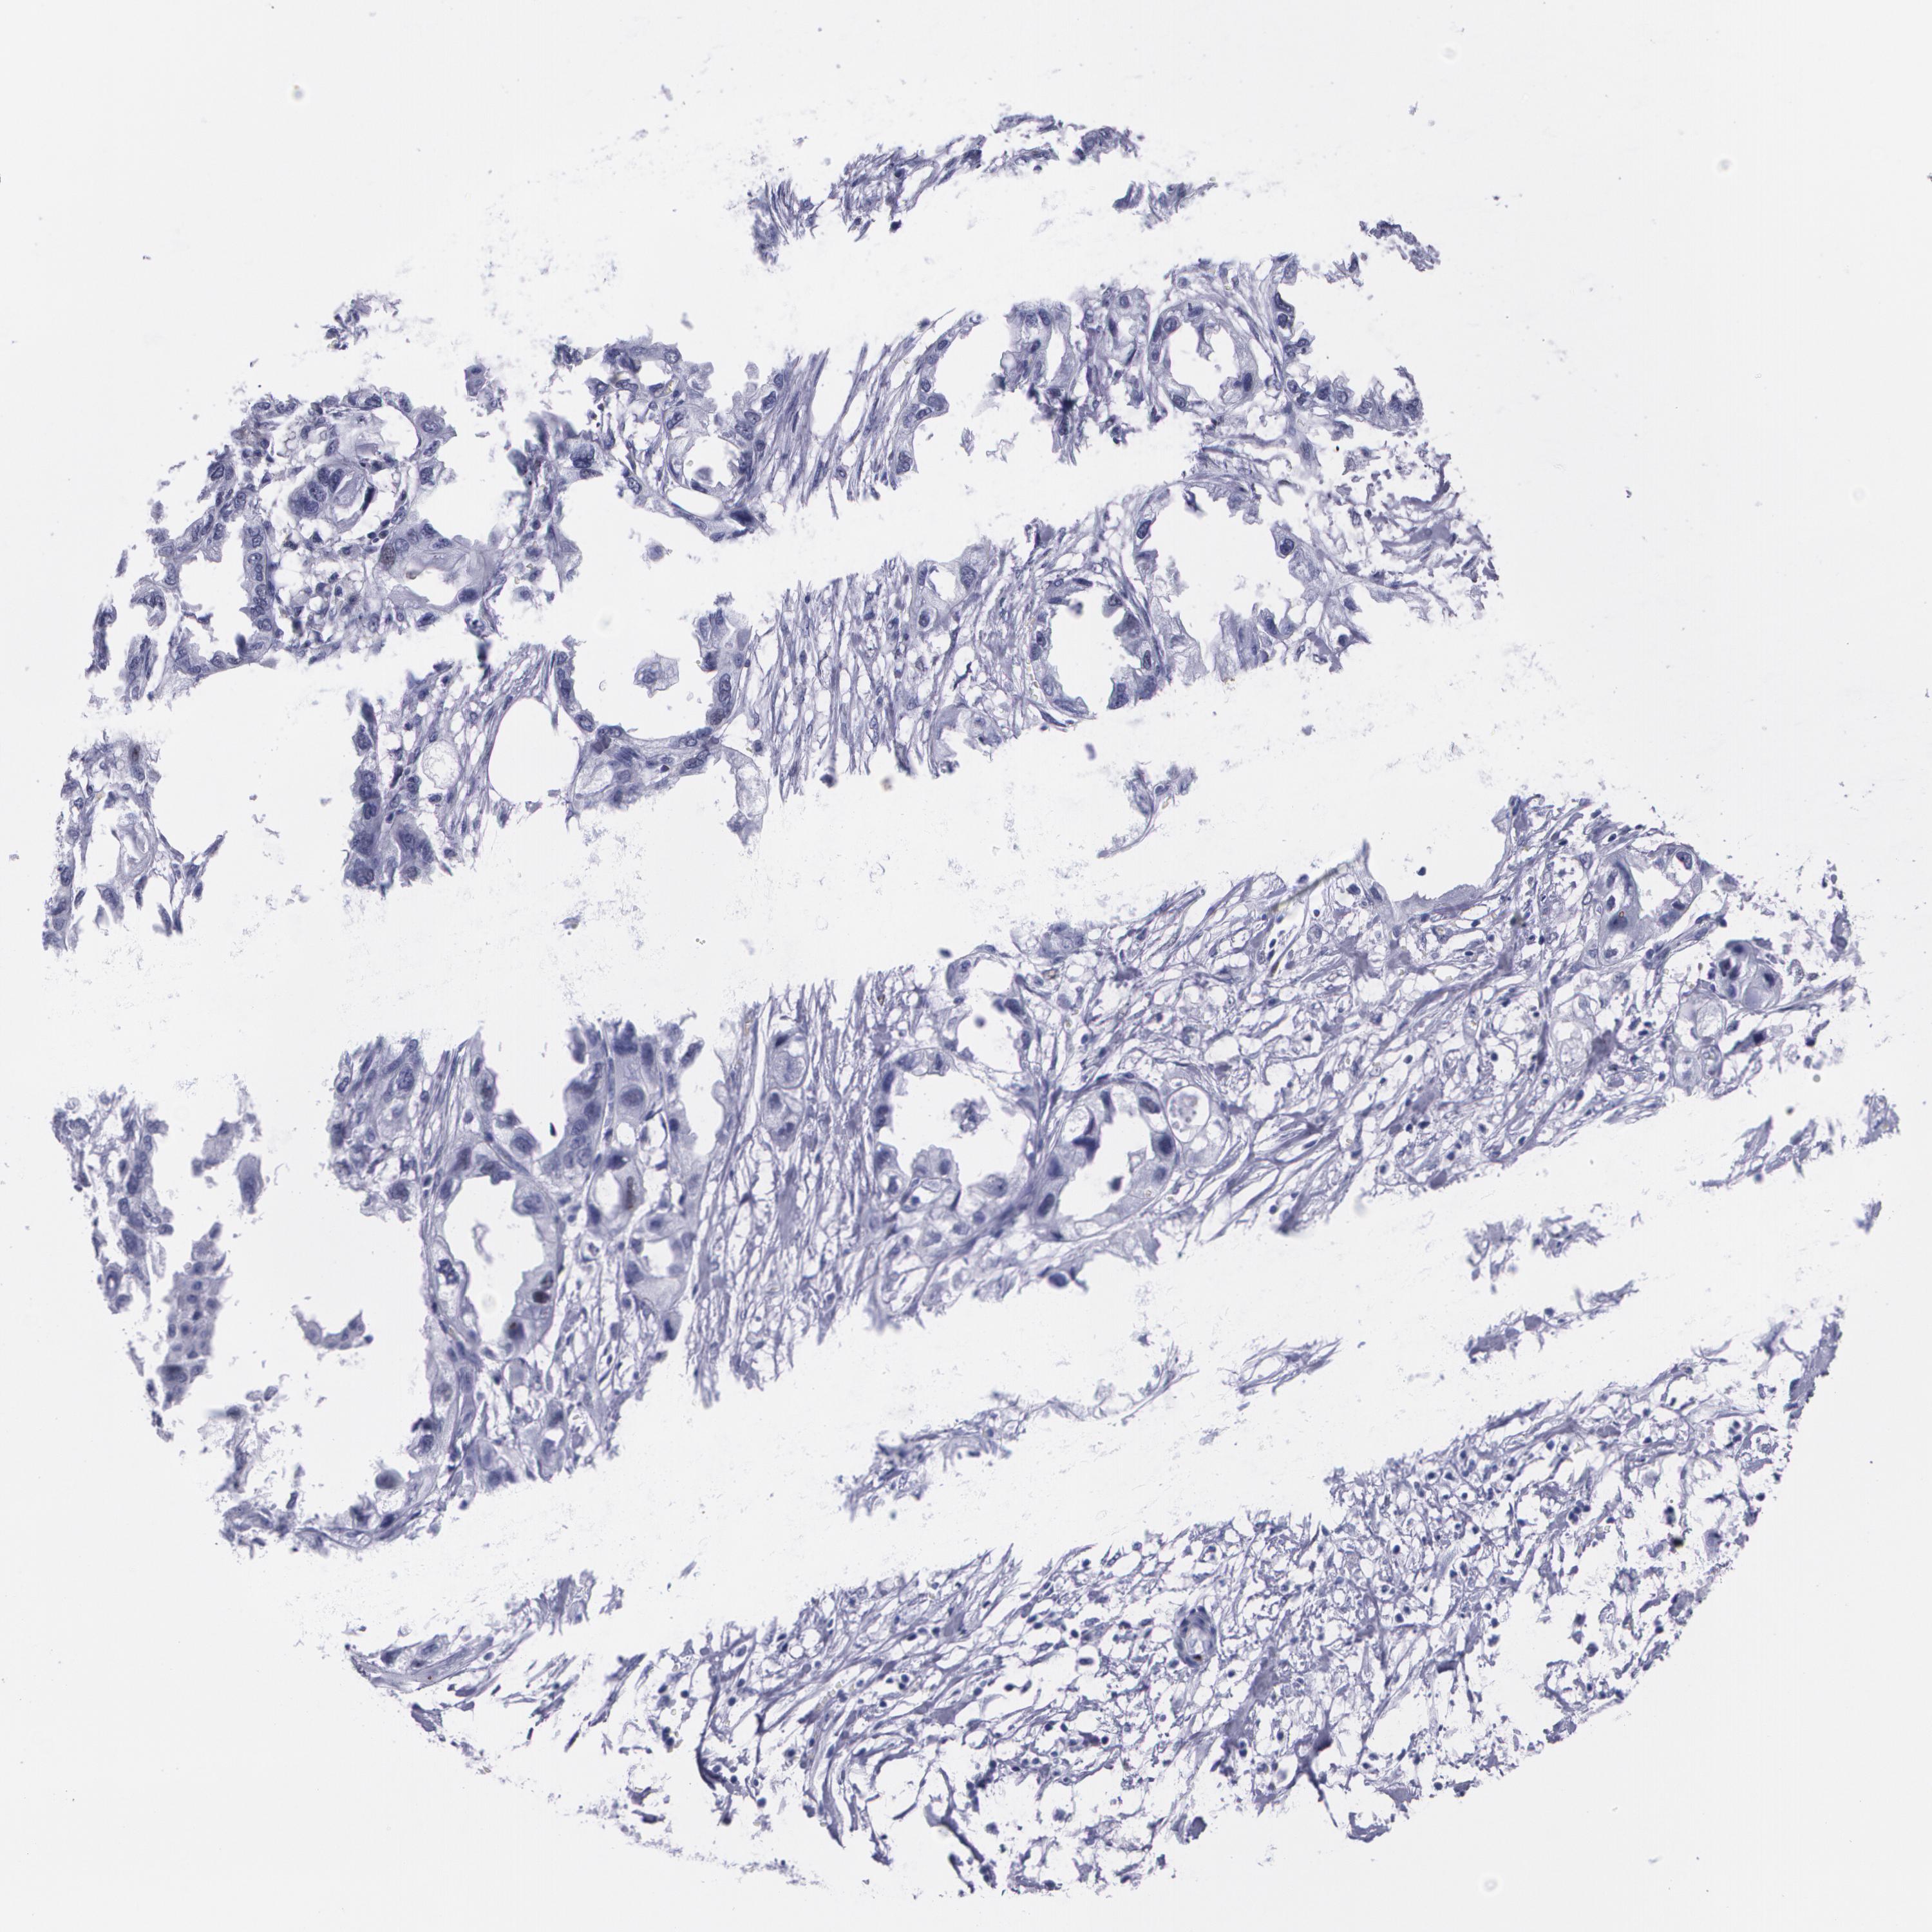

ENDOMETRIAL CANCER - Protein expressioni

A mouse-over function shows sample information and annotation data. Click on an image to view it in a full screen mode. Samples can be filtered based on level of antibody staining by selecting one or several of the following categories: high, medium, low and not detected. The assay and annotation is described here.

Note that samples used for immunohistochemistry by the Human Protein Atlas do not correspond to samples in the TCGA dataset.

Antibody stainingi

Antibody staining in the annotated cell types in the current human tissue is reported as not detected, low, medium, or high, based on conventional immunohistochemistry profiling in selected tissues. This score is based on the combination of the staining intensity and fraction of stained cells.

Each image is clickable and will lead to virtual microscopy that enables deeper exploration of all samples and also displays staining intensity scores, fraction scores and subcellular localization as well as patient and tissue information for each sample.

Antibody CAB002973

Antibody CAB039238

Antibody CAB039239

Antibody CAB072876

Staining

High

Medium

Low

Not detected

Intensity

Strong

Moderate

Weak

Negative

Quantity

>75%

75%-25%

<25%

None

Location

Nuclear

Cytoplasmic/membranous

Cytoplasmic/membranous,nuclear

Adenocarcinoma, NOS

Neoplasm, malignant, NOS

Adenocarcinoma, metastatic, NOS